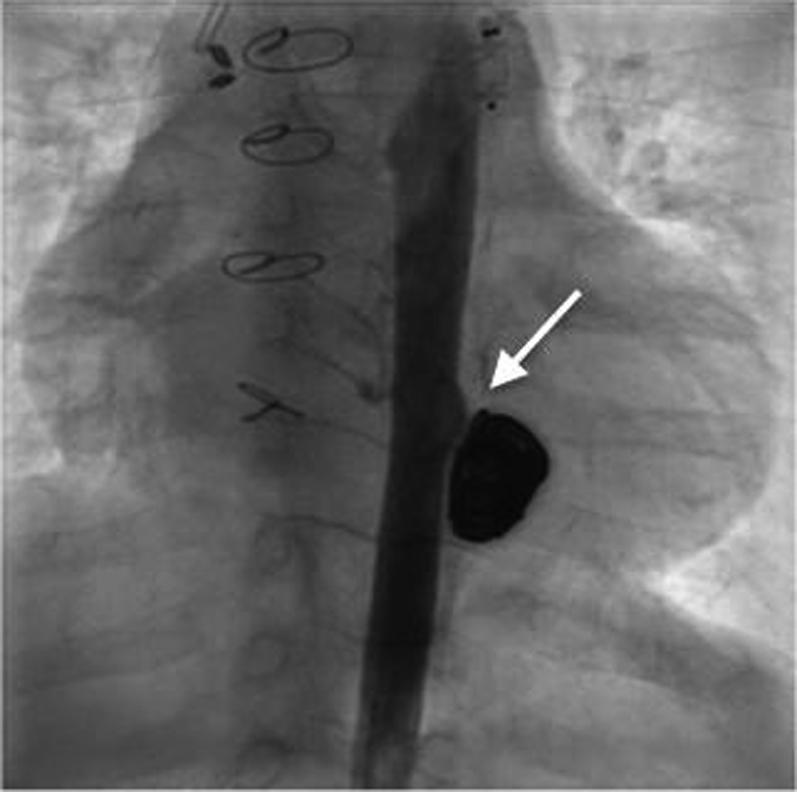

Pediatric aortic pseudoaneurysms are rare and can result in life-threatening sequelae. We describe 2 cases of exclusion of descending thoracic aortic pseudoaneurysm by different approaches, chosen based on the anatomy and cause of the lesions. ().

小儿主动脉假性动脉瘤较为罕见,可导致危及生命的后遗症。我们描述了2例通过不同方法排除降主动脉假性动脉瘤的病例,这些方法是根据病变的解剖结构和病因选择的。()